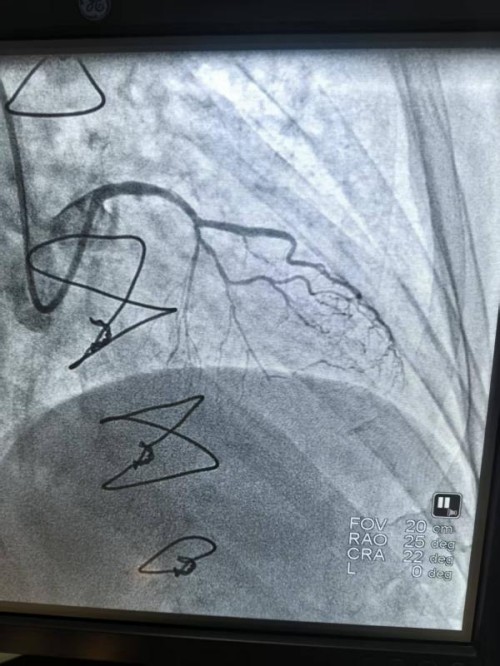

入院后,彭文华主任团队为刘大爷进行了全面检查。冠脉造影结果让医生们皱起了眉头:之前搭的桥血管是通畅的,但心脏自身的重要血管(前降支至对角支)出现了严重的狭窄,狭窄程度超过90%。更棘手的是,这个狭窄部位伴随着严重的钙化。通俗点说,就是血管壁里沉积了厚厚的“钙质”,像水管里结满了坚硬的水垢,甚至像在血管里筑起了“钢筋水泥”,让普通的介入器械难以通过,强行处理风险极高。

造影图像清晰地显示,病变处的钙化长且弥漫,呈管状钙化影。而且是深埋在血管壁中层的“深层钙化”。面对如此复杂的病情,常规的球囊扩张就像用普通气球去撑开一块石头,不仅可能撑不开,还容易把血管壁撑破,导致夹层、穿孔等严重并发症。

在4个大气压的低压下,球囊开始工作,释放出脉冲式冲击波。“砰、砰、砰……”伴随着几十次轻柔的脉冲,冲击波能量穿透血管,直抵深处的钙化病灶。术后再次用造影查看,效果立竿见影。血管管腔瞬间变得宽敞了许多,而且血管壁完好无损,没有出现任何夹层或损伤。